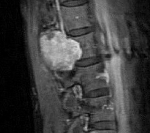

Раннее выявление экстрамедуллярных опухолей затруднено из-за их «маскировки» симптоматикой обычного радикулита или соматических заболеваний. Заподозрить опухолевый процесс позволяет отсутствие улучшения от проводимого лечения. Для того, чтобы своевременно диагностировать экстрамедуллярные опухоли, необходимо проводить МРТ позвоночника всем пациентам с корешковым синдромом. Однако это не всегда возможно из-за существенной стоимости МРТ.

Однако наиболее достоверным методом, визуализирующим экстрамедуллярные опухоли является магнитно-резонансная томография. Она дает возможность определить точное расположение, распространенность, форму опухоли, предположить ее вид, оценить степень спинальной компрессии. При наличии противопоказаний к МРТ альтернативным методом выступает КТ-миелография. При опухолях сосудистого генеза дополнительно назначается спинальная ангиография. Точно судить о доброкачественности опухоли и ее виде позволяет гистологическое исследование её тканей, забор которых, как правило, производится интраоперационно.